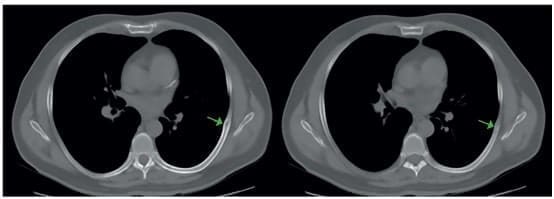

Fue valorado en la clínica CardioVID, en Medellín, Colombia, por dolor torácico izquierdo de tres meses de evolución, se realizó una tomografía de tórax, observando una lesión lítica de borde escleroso de 13 x 6 mm, localizada en la cara lateral del séptimo arco costal izquierdo, con engrosamiento del espacio pleural y ruptura de la cortical medial y lateral, sin masa sólida acompañante (figura 1).

Figura 1. Corte axial de la tomografía en la que se observa la lesión lítica en el séptimo

arco costal (flecha verde).